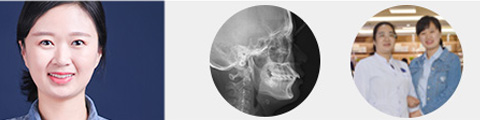

矫正

唯美口腔连锁·汇聚实力专家